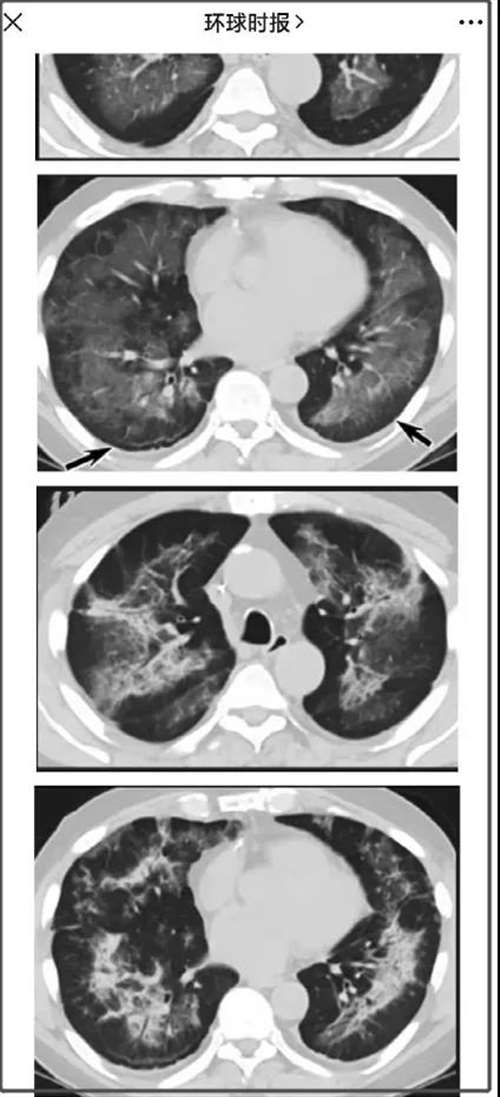

而根据现在一些媒体,拿着当时电子烟肺炎病人的一些CT照片照专家咨询

结果专家认为,这些电子烟肺炎的CT图片跟新冠病毒的病例很相似,比如都有毛玻璃样阴影,这是一种肺部积液形成白斑的现象,是新冠病毒感染后的很典型特征。

所以,有专家认为,2019年美国报道的电子烟肺炎病例里,有可能存在新冠病毒感染的病例。